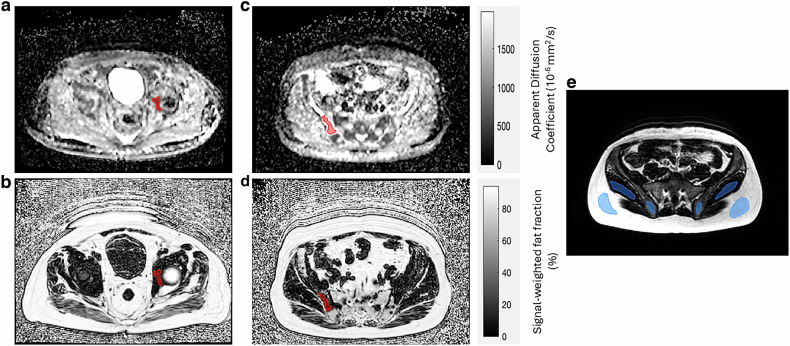

目的:本研究旨在评估临床可用的Dixon序列在转移性前列腺癌患者正常骨髓和骨盆骨转移中脂肪分数估计的准确性。方法:对转移性前列腺癌患者和健康志愿者进行前瞻性单中心研究。根据6点PDw梯度回声(q-Dixon)序列测量参考标准质子密度脂肪分数,评估临床可用Dixon序列估计脂肪分数的线性和偏倚。病变脂肪分数估计值使用Friedman检验进行交叉比较。用Bland-Altman图评价志愿者的重复性。利用TSE-Dixon序列估算脂肪组分对特定吸收率(SAR)相关修饰的敏感性用相关图进行评估。结果:33例患者被纳入本研究。结论:T1w Dixon方法可以检测到治疗后的变化,但仍受放松时间偏差的影响。虽然所有的Dixon方法都显示出良好的重复性,但谨慎选择与sar相关的修饰对于保持PD-和t2加权TSE序列的准确性至关重要。信号加权脂肪分数估计与质子密度脂肪分数表征转移性骨病变的临床有效性尚未得到充分评估。t1加权Dixon序列符合全身MRI国际指南,显示出明显的脂肪部分偏倚,特别是在病变和肌肉中。使用国际指南中推荐的t1加权Dixon序列进行脂肪分数估计对松弛时间偏差高度敏感,使得潜在的生理变化可能不明确。

Objective: This study aimed to assess the accuracy of fat fraction estimation with clinically available Dixon sequences in normal-appearing marrow and bone metastases in the pelvis of metastatic prostate cancer patients.

Methods: A prospective single-centre study was conducted with metastatic prostate cancer patients and healthy volunteers. Linearity and bias of fat fraction estimates from clinically available Dixon sequences were assessed against a 6-point PDw gradient echo (q-Dixon) sequence measuring the reference standard proton density fat fraction. Lesion fat fraction estimates were cross-compared using the Friedman test. Repeatability in volunteers was evaluated with Bland-Altman plots. Sensitivity of fat fraction estimates using TSE-Dixon sequences to specific absorption rate (SAR) related modifications were evaluated with correlation plots.

Results: Thirty-three patients were recruited for this study. Significant (p < 0.05) absolute bias (12.4%) was demonstrated in the T1-weighted (T1w) Dixon measurements against the q-Dixon. Significant differences (p < 0.05) between fat fraction estimates provided by the T1w Dixon and PDw Dixon sequences were observed in 13 active and 6 treated lesions. Repeatability coefficients for fat fraction estimates ranged from 5.9 to 9.0% in the pelvic tissues of healthy volunteers. Reduction of slice number with repetition time for SAR had the greatest effect, reaching a maximum difference in fat fraction of 14.7% from the q-Dixon for the T2w-TSE Dixon in bone marrow.